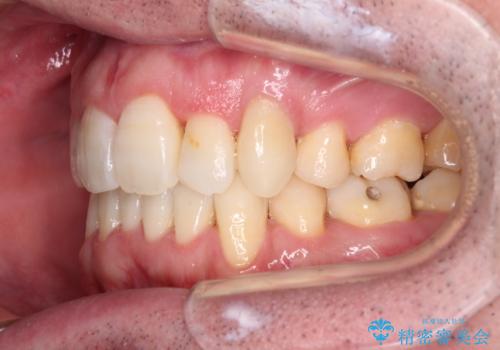

ものが挟まる 著しい叢生を解消 ワイヤー装置による抜歯矯正

- 審美装置

- 前歯のデコボコを気にして来院された患者様です。

叢生の解消とともに、前方に張り出した上顎前歯を引っ込めることを目的とし、上下左右の第一小臼歯4歯を抜歯をしてワイヤー矯正により治療することとしました。

治療開始直後は、あっという間に歯列が整い、すぐに終わるのではないかと思われましたが、治療の後半にブラックトライアングル解消のための処置を行ったため、当初予定していた2年半ほどの期間を要することとなりました。